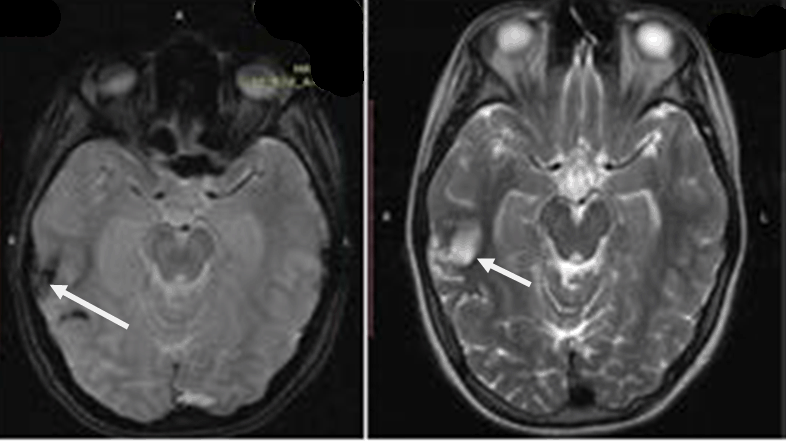

A few months later, a repeat MRI scan was performed, while the patient being neurologically normal. The examination verified the known lesion at the right temporal-occipital lobe region, which revealed characteristics, compatible with a chronic lesion. More specifically, the imaging of the lesion identified a territory with intermediate to hypo-intensity signal at FLAIR sequences and hemosiderin ring at T2-GRE sequences (Figure 8).

Figure 8: The left image is an MRI GRE sequence, showing the hemosiderin ring (arrow) and the right image is a FLAIR sequence, revealing an area of intermediate to hypo intensity signal (arrow).